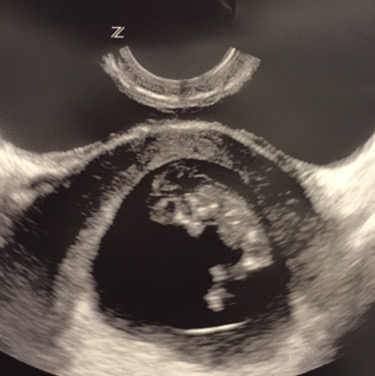

So, my lobster was 6 days behind but everything looks perfect. Late implantation seems to be the cause and that happened with my first pregnancy, too. It's probably a boy.